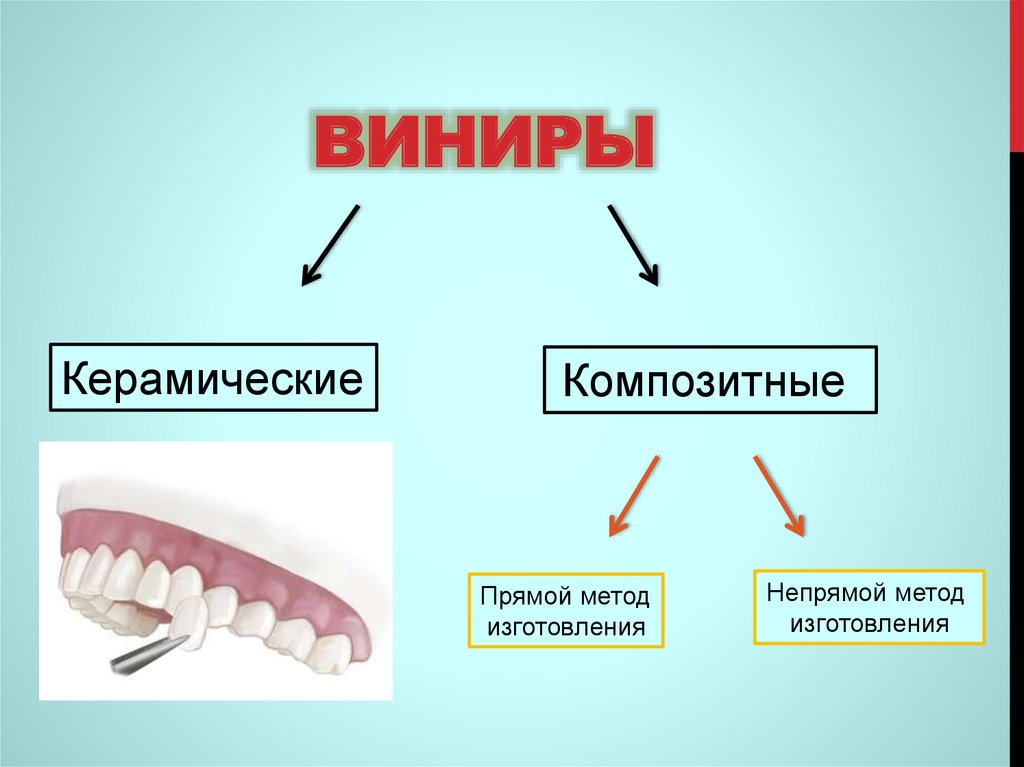

При подготовке к установке виниров важно правильно подобрать цвет и форму, обратитесь к специалистам за консультацией.

Виниры. Все этапы установки и изготовления - Зубы до и после установки виниров - Дентал ТВ 12+